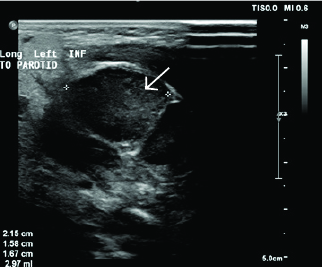

Typically, patients are febrile and have significant pain on neck movement, which can mimic meningismus. Soft tissue neck ultrasound or computed tomography (CT) may be helpful in defining the extent of abscess or surrounding cellulitis. (See Figures 1 and 2.) Empirical treatment of acute bacterial cervical lymphadenitis should provide adequate coverage for both Staphylococcus aureus, including community-associated methicillin-resistant S. aureus (CA-MRSA) if indicated by local microbiology patterns, and group A beta hemolytic Streptococcus.4 The initial drug of choice is amoxicillin/clavulanate potassium (Augmentin), although clindamycin is preferred where MRSA has high prevalence.4 Nodes with abscess formation may need incision and drainage if they show no improvement despite 48 hours of antibiotic treatment. Acute group A streptococcal (GAS) pharyngitis also may present with bilateral cervical lymphadenitis and is discussed later.

Figure 1. Enlarged Node in Cervical Lymphadenitis |

Image courtesy of Derya Caglar, MD. |

Figure 2. Enlarged Node in Cervical Lymphadenitis, Measuring |